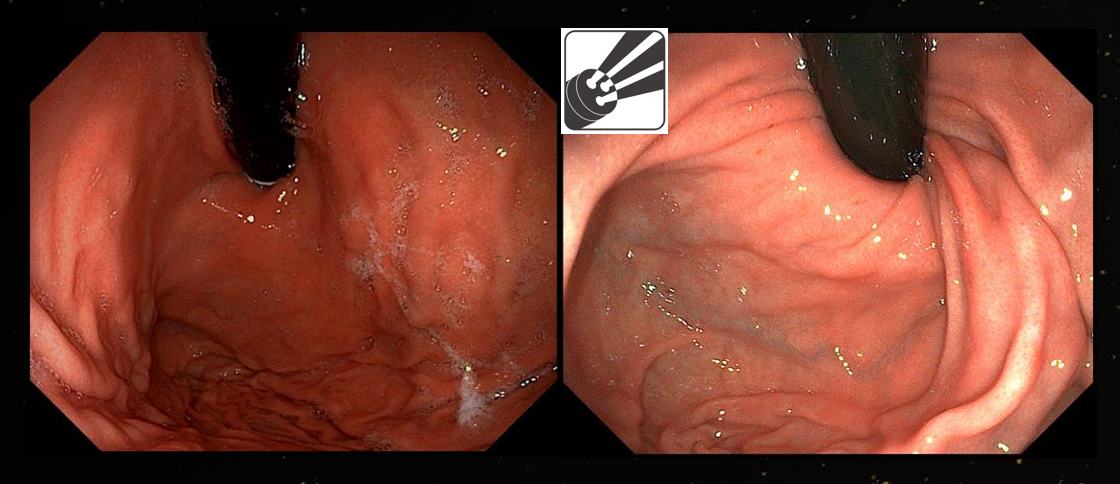

Với độ phân giải cao đạt 3840x2160P, máy nội soi Aohua AQ-300 mang tới sự cải tiến vượt bậc trong độ chi tiết và sắc nét của hình ảnh. Số lượng điểm ảnh cao giúp ghi lại được nhiều chi tiết hơn về cấu trúc và hình thể. Mang lại trải nghiệm hình ảnh rõ nét và sống động.

Hình ảnh nội soi đại tràng bằng máy nội soi Aohua AQ-300

3 dây dẫn sáng

Ống soi được thiết kế 3 dây dẫn sáng có độ lớn bằng nhau giúp trường nhìn được chiếu sáng tốt và đồng đều hơn.

Công nghệ lấy nét kép

Dây soi với công nghệ lấy nét kép cho hình ảnh rõ nét và chi tiết hơn. Dễ dàng chuyển đổi giữa chế độ lấy nét bình thường và lấy nét kép bằng 1 thao tác trên tay cầm.